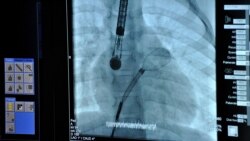

Оклюдер – це серцевий імплантат, який «закриває дірку» при дефекті перегородок серця. Він може розтягуватися в довгу трубочку і приймати форму парасольки розміром до 4 см. Його вводять через невеликі проколи на стегні, щоб він судинами рухався до серця. Після того, як оклюдер у вигляді складеної парасольки досягає отвору, його відкривають і фіксують. Із часом сполучна тканина проростає в нього, і оклюдер стає частиною серця.